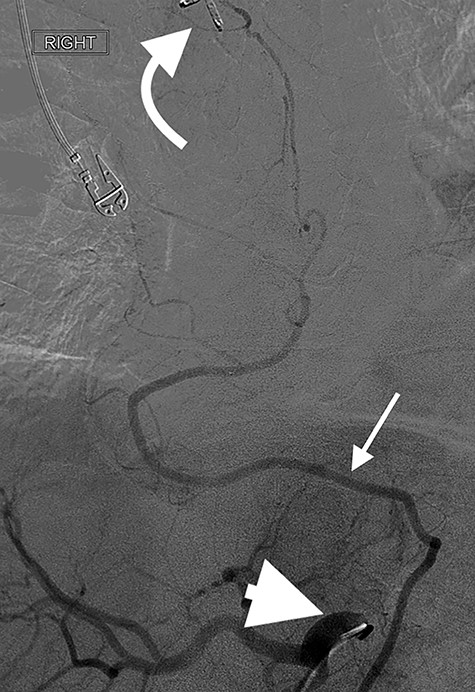

Angiography of the right gastro-epiploic artery. Arrowhead = celiac trunk; Arrow = right gastro-epiploic; Curved arrow = OG anastomosis.

Eight days later, he represented with an upper gastrointestinal bleed with massive haematemesis requiring immediate intubation for airway protection. Computer tomography angiography was unremarkable and an emergency gastroscopy revealed an extensive amount of blood and clot in the oesophagus and gastric conduit (limiting the view), but no active bleeding point. Conservative treatment in the Intensive Care Unit (ICU) with blood transfusion, proton pump inhibitors and life support were implemented. Another large bleed occurred 2 days later and a repeat gastroscopy revealed a non-bleeding visible vessel at the OG anastomosis and a haemostatic clip was applied. However, over the next 10 days, the patient remained blood transfusion dependent and had two further endoscopies. The first was unremarkable, but the second endoscopy re-demonstrated the luminal vessel at the OG anastomosis, with no evidence of the previously placed clip. This was felt to be the cause of his intermittent and problematic bleeding, so another haemostatic clip was attempted, resulting in pulsatile, moderate volume arterial bleeding. The procedure was abandoned and the patient transported immediately to the Interventional Radiology Suite. Right femoral access was obtained and angiography performed. The thoracic aorta was normal, so the celiac trunk was cannulated and angiography of the right gastro-epiploic artery performed (Fig. 1), revealing active extravasation of contrast at the OG anastomosis as shown in Fig. 2. A microcatheter was advanced along the length of the right gastro-epiploic artery to the OG anastomosis and coil embolization was performed (Fig. 3). Care had to be taken to ensure that the embolization was as distal as possible to limit the risk of ischaemic complications. The patient required lengthy ongoing care in the ICU for organ dysfunction but remained hemodynamically stable after embolization without evidence of conduit ischaemia. His hospital stay was obviously lengthy, but he was ultimately transferred to a rehabilitation unit.

Oesophagectomy is a major operation with significant perioperative morbidity. Respiratory and cardiac complications, along with gastric conduit ischemia and anastomotic leak, tend to dominate [3]. However, bleeding complications apart from those occurring intra-operatively are rarely reported [1, 2]. We present a unique case of an anastomotic bleed from a terminal branch of the gastro-epiploic vascular arcade. While the origin of this vascular arcade is a defined vessel (right gastric-epiploic artery) visible to the naked eye, the terminal portion is comprised of submucosal arterioles and capillaries and often devoid of a visible vessel [4]. However, as shown in Fig. 1, vascular supply to the terminal portion of the gastric conduit is present and can be abundant. The bleeding in this case likely occurred from incorporation in the anastomosis of either an invisible submucosal arteriole or the terminal portion of the right gastro-epiploic artery hidden within omental tissue. It is our standard practise to construct the OG anastomosis with the EEA circular stapler. It is common surgical knowledge that the oesophageal wall is thick [5] and has been our practise to use the 4.8-mm EEA staple height. There are several descriptions in the literature about this anastomotic technique and most recommend this staple height [6–8]. However, we believe that the higher staple height may have contributed to the bleeding issue in this case as there may have been insufficient compression of a submucosal arteriole. While it is impossible to be certain if a lower staple height would have prevented this situation, this case has resulted in our change to use the 3.5-mm EEA. In addition to this, we have become more meticulous in ensuring that the portion of the great curvature to be used for the anastomosis is cleared of excessive omental tissue to be sure no visible vessel is present that may get caught in the anastomosis.